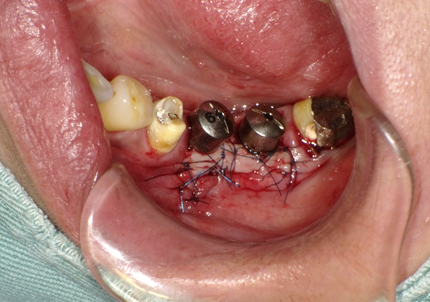

9.左下3本最終補綴装着(2021年11月)

10.口腔内写真(2022年2月)

特に問題無く経過はとても良いです。

患者様ご本人も「良く咬めてとても良い」と満足されています。